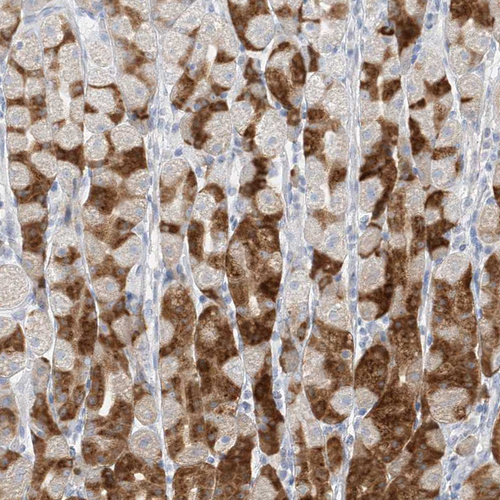

Immunohistochemistry analysis in human stomach and skeletal muscle tissues using HPA031718 antibody. Corresponding PGC RNA-seq data are presented for the same tissues.